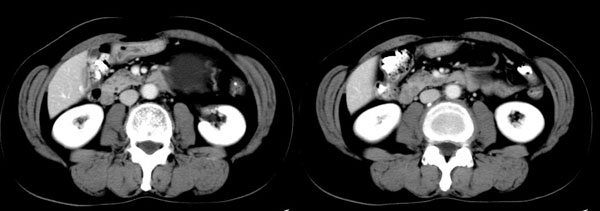

女性,58岁。卵巢癌术后4年余,无不适。体检b超发现左上腹肿块。

ct平扫加增强扫描:胆囊折叠,壁厚,其内见结石。胰腺体尾部见一5.8x7.5cm囊性肿物,ct值12hu,壁薄,增强扫描未明显强化,胰头不大,强化均匀。

ct诊断:1.胆囊炎,胆囊折叠并结石。

2.胰体尾部囊肿。